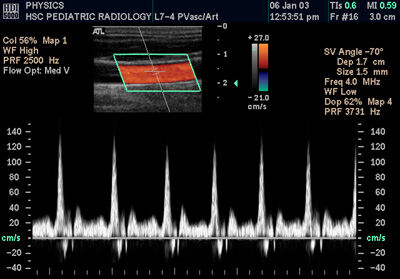

Spectral Doppler of Common Carotid Artery

Sonography can be enhanced with Doppler measurements, which employ the Doppler effect to assess whether structures (usually blood) are moving towards or away from the probe, and its relative velocity. By calculating the frequency shift of a particular sample volume, for example a jet of blood flow over a heart valve, its speed and direction can be determined and visualised. This is particularly useful in cardiovascular studies (sonography of the vasculature system and heart) and essential in many areas such as determining reverse blood flow in the liver vasculature in portal hypertension. The Doppler information is displayed graphically using spectral Doppler, or as an image using color Doppler (directional Doppler) or power Doppler (non directional Doppler). This Doppler shift falls in the audible range and is often presented audibly using stereo speakers: this produces a very distinctive, although synthetic, pulsing sound.